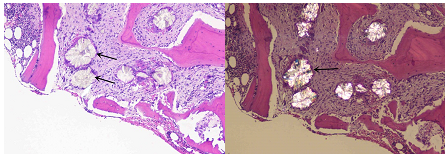

The inexplicable blood cell deficiency prompted a bone marrow aspiration and biopsy. There were many osteoblasts and osteoclasts close to bony trabeculae, along with localized trabecular resorption, in the bone marrow, which was found to be normocellular to slightly hypercellular. Additionally, there were areas of marrow fibrosis. Many needle-like, refractile crystals were grouped together in the marrow spaces, encircled by a massive cell reaction that is characteristic of a foreign body. These crystals exhibited strong birefringence when exposed to polarized light, which is consistent with the buildup of calcium oxalate (bone marrow oxalosis). The patient was diagnosed with Primary Hyperoxaluria with bone marrow oxalosis based on the patient's early-stage chronic kidney disease, long history of kidney stones, and unique bone marrow findings.

Figure 2: Bone marrow showing oxalate crystals can be seen in bone marrow with extensive starburst crystal deposition. Photographed in partly polarized light at ×40.